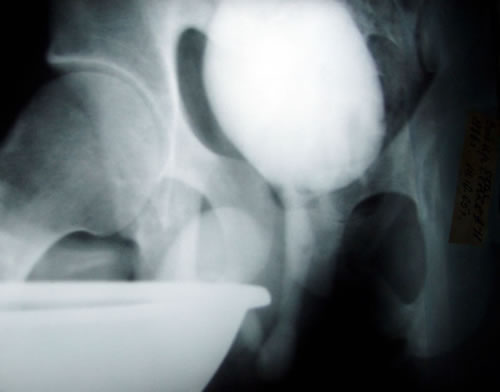

Рентгенография:

2. Микцонная цистография